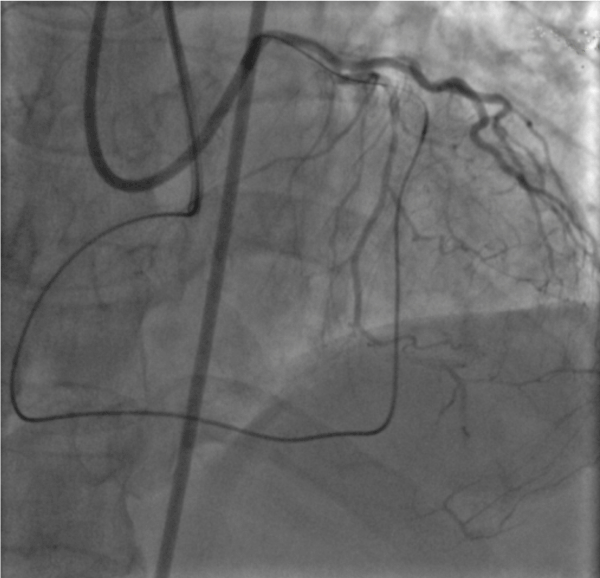

The advanced greeting technique

Figure 1E. The 4F child catheter was advanced to the distal of the occluded stent using an anchor balloon technique. The arrow indicates the tip of the child catheter.